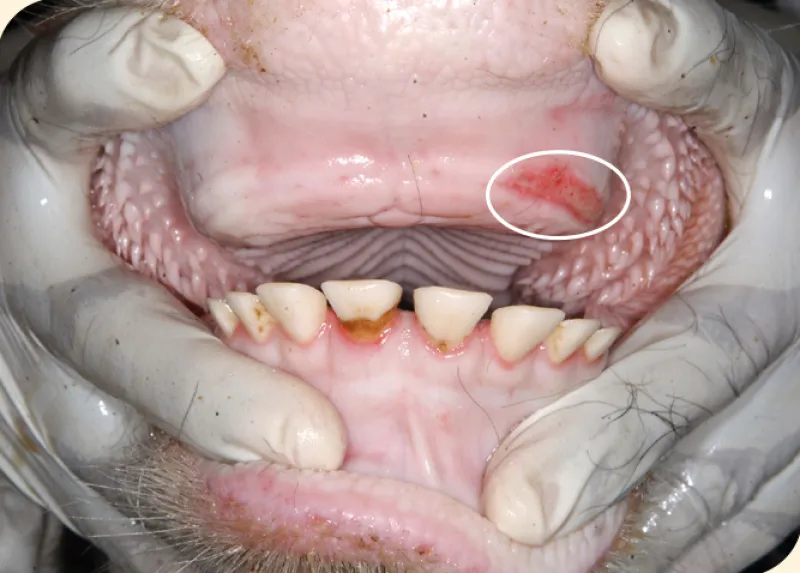

Signs of FMD can range from mild to severe and tend to be more severe in cattle and pigs than sheep and goats. The hallmark signs of FMD are fever and blister-like sores.

• Blisters and sores: Blisters may develop in the mouth or on the tongue, teats and hooves. These blisters can rupture, leaving raw erosions in the tissue. The painful sores can result in additional symptoms, including the following:

The signs of FMD are indistinguishable from other blister/erosion-causing diseases found in the U.S., such as vesicular stomatitis and bluetongue. The only way to determine the cause is through diagnostic testing. Contact your local veterinarian or the state veterinarian for testing.